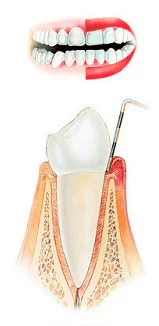

Стадии пародонтита

Здоровый зуб |

1 стадия |

2 стадия |

3 стадия |

4 стадия |

До недавнего времени в Омске использовали только очень болезненный способ лечения пародонтита с помощью уколов, теперь в нашей клинике применяется инновационный безболезненный подход к лечению десен с мощью лазера. Прочитать подробнее о лечении пародонтита с помощью лазера.

Стоимость лечения пародонтита около 5 000 ₽, конечная стоимость зависит от степени поражения. Пародонтит также как и чистку зубов необходимо делать регулярно (раз в пол года, максимум 1 раз в год), при этом лечение пародонтита стоит в 2 раза дороже!